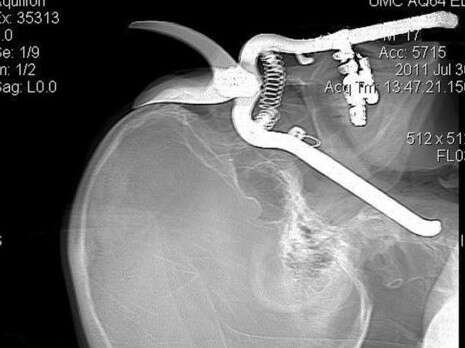

תושב אריזונה בן 86 שעבד בגינה נפל עם פניו כלפי המזמרה, שחדרה לעינו ומשם לגרונו. המנתחים הצליחו להציל את העין

הקשיש, לירוי לוטצ'ר מגרין ואלי, אריזונה, עבד בגינה כאשר הפיל את המזמרה, וכשהתכופף להרימה איבד את שיווי משקלו ונפל כשפניו כלפיה. המזמרה חדרה לארובת

עינו והגיעה דרכה עד לגרונו.

המנתחים הוציאו את המזמרה מעינו של לוטצ'ר והצליחו להצילה. "לא הייתם מאמינים למראה עיניכם", סיפרה על המקרה אחת הרופאות שטיפלה בקשיש. מהמרכז הרפואי נמסר כי כעת סובל לוטצ'ר מנפיחות ומנזק קל בלבד לעין הפגועה.

צילום הרנטגן של הקשיש לאחר חדירת המזמרה